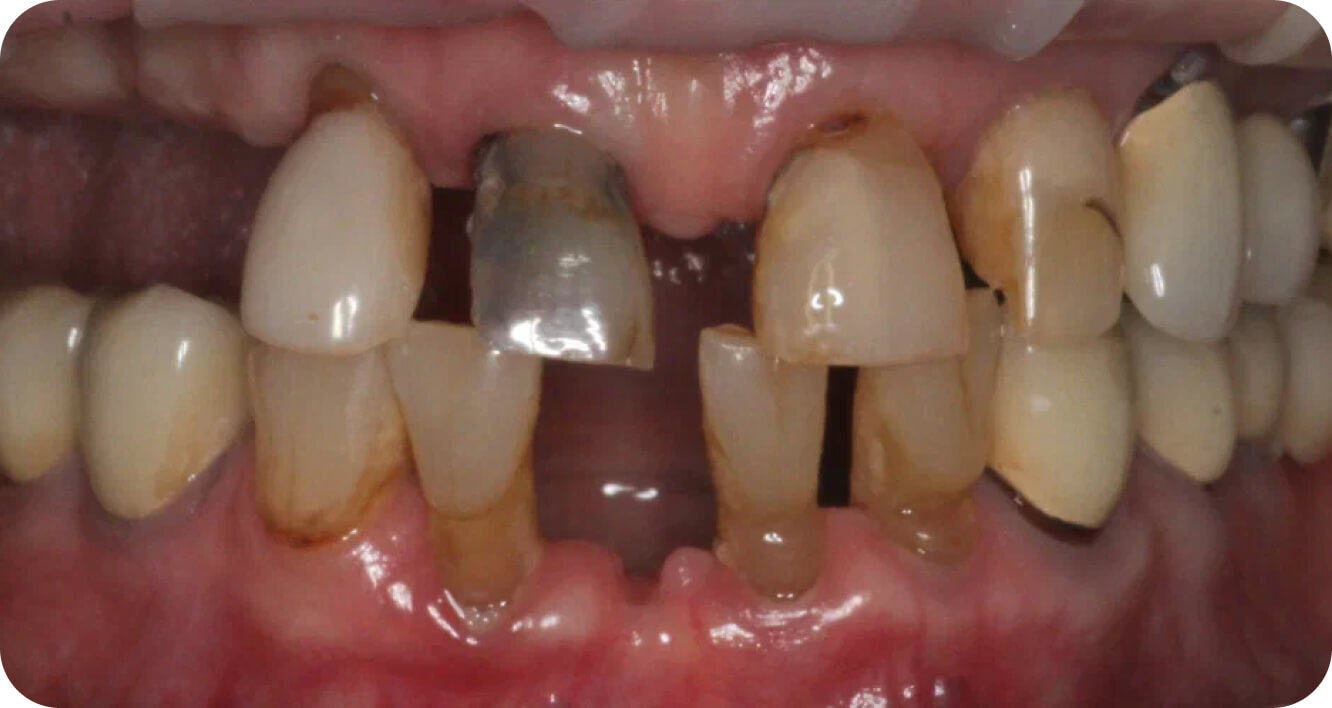

Мои работы

до/после

Большие

работы